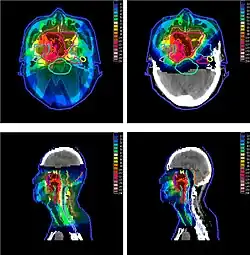

The figure at the right of the page shows how beams of X-rays (IMRT; left frame) and beams of protons (right frame), of different energies, penetrate human tissue. A tumor with a sizable thickness is covered by the IMRT spread out Bragg peak (SOBP) shown as the red lined distribution in the figure. The SOBP is an overlap of several pristine Bragg peaks (blue lines) at staggered depths.

Megavoltage X-ray therapy has less "skin sparing potential" than proton therapy: X-ray radiation at the skin, and at very small depths, is lower than for proton therapy. One study estimates that passively scattered proton fields have a slightly higher entrance dose at the skin (≈75%) compared to therapeutic megavoltage (MeV) photon beams (≈60%).[3] X-ray radiation dose falls off gradually, needlessly harming tissue deeper in the body and damaging the skin and surface tissue opposite the beam entrance. The differences between the two methods depends on: